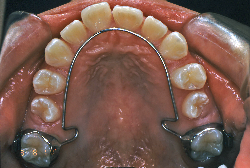

診断の結果、典型的なアングル2級1類の上顎前突です。上下歯列の正中の不一致も見られます。しかし、歯の大きさは平均値に近く、配列の凸凹がそれほど見られません。このまま放置すると、将来的には抜歯を伴う矯正治療を行う可能性が高くなりますが、このタイミングで適切な治療をすると、非抜歯治療が可能かもしれません。

矯正歯科医が着目するのは、奥歯の噛み合わせの位置関係です。前歯の位置にそれなりの差が生じていても、奥歯の位置が正しければそれほど重症という評価にはなりません。このケースの場合は、上下の第一大臼歯の位置関係は、直線的に一致しているタイプでした(矢印が一致)。混合歯列時期の奥歯の位置関係としては、ほぼ正常な状態といえますが、症状から言うと、上の奥歯をもっと後ろに下げてやることができれば、上顎歯列全体に余裕ができるので、凸凹も解消できるし、前歯の傾きを内向きに修正することもできると考えられました。しかしこのまま全体に永久歯が生えきってしまうと、上の前歯が出たままになってしまいますので、生え替わりが完了する前に大急ぎで奥歯を後ろに下げる必要があると判断しました。

こういう症状でもっとも効果があるのが、顎外固定装置と言って、お口の外部から奥歯に力をかける方法です。 写真の装置はネックバンドというタイプの装置です。この装置は取り外し式ですので、夜寝るときに毎日自分で取り付けて、寝ている間に少しずつ上の奥歯を後ろに下げていきます。この装置には、奥歯を後ろに下げる効果だけでなく、上顎の過剰な成長発育の抑制、下顎の成長促進作用があるとされており、上顎前突の症状にはいずれも有利な効果が期待できます。

ネックバンドを1年半使用して、上顎大臼歯が十分後ろに下がったところで、裏側にリンガルアーチという固定のワイヤーを取り付けて、新しく生じた隙間が狭くならないよう「保隙(ほげき)」という処置をして、永久歯が生えそろうまで待機中の様子です。配列全体に隙間が生じているのがお分かりいただけると思います。これだけの隙間が確保できていれば、抜歯をしなくても、あとで上の前歯を内側に理想的な角度で引っ込めることができます。このように完全に永久歯列になる前に、十分な隙間が確保できるかどうかが、非抜歯で矯正できるかどうかの分かれ目になります。